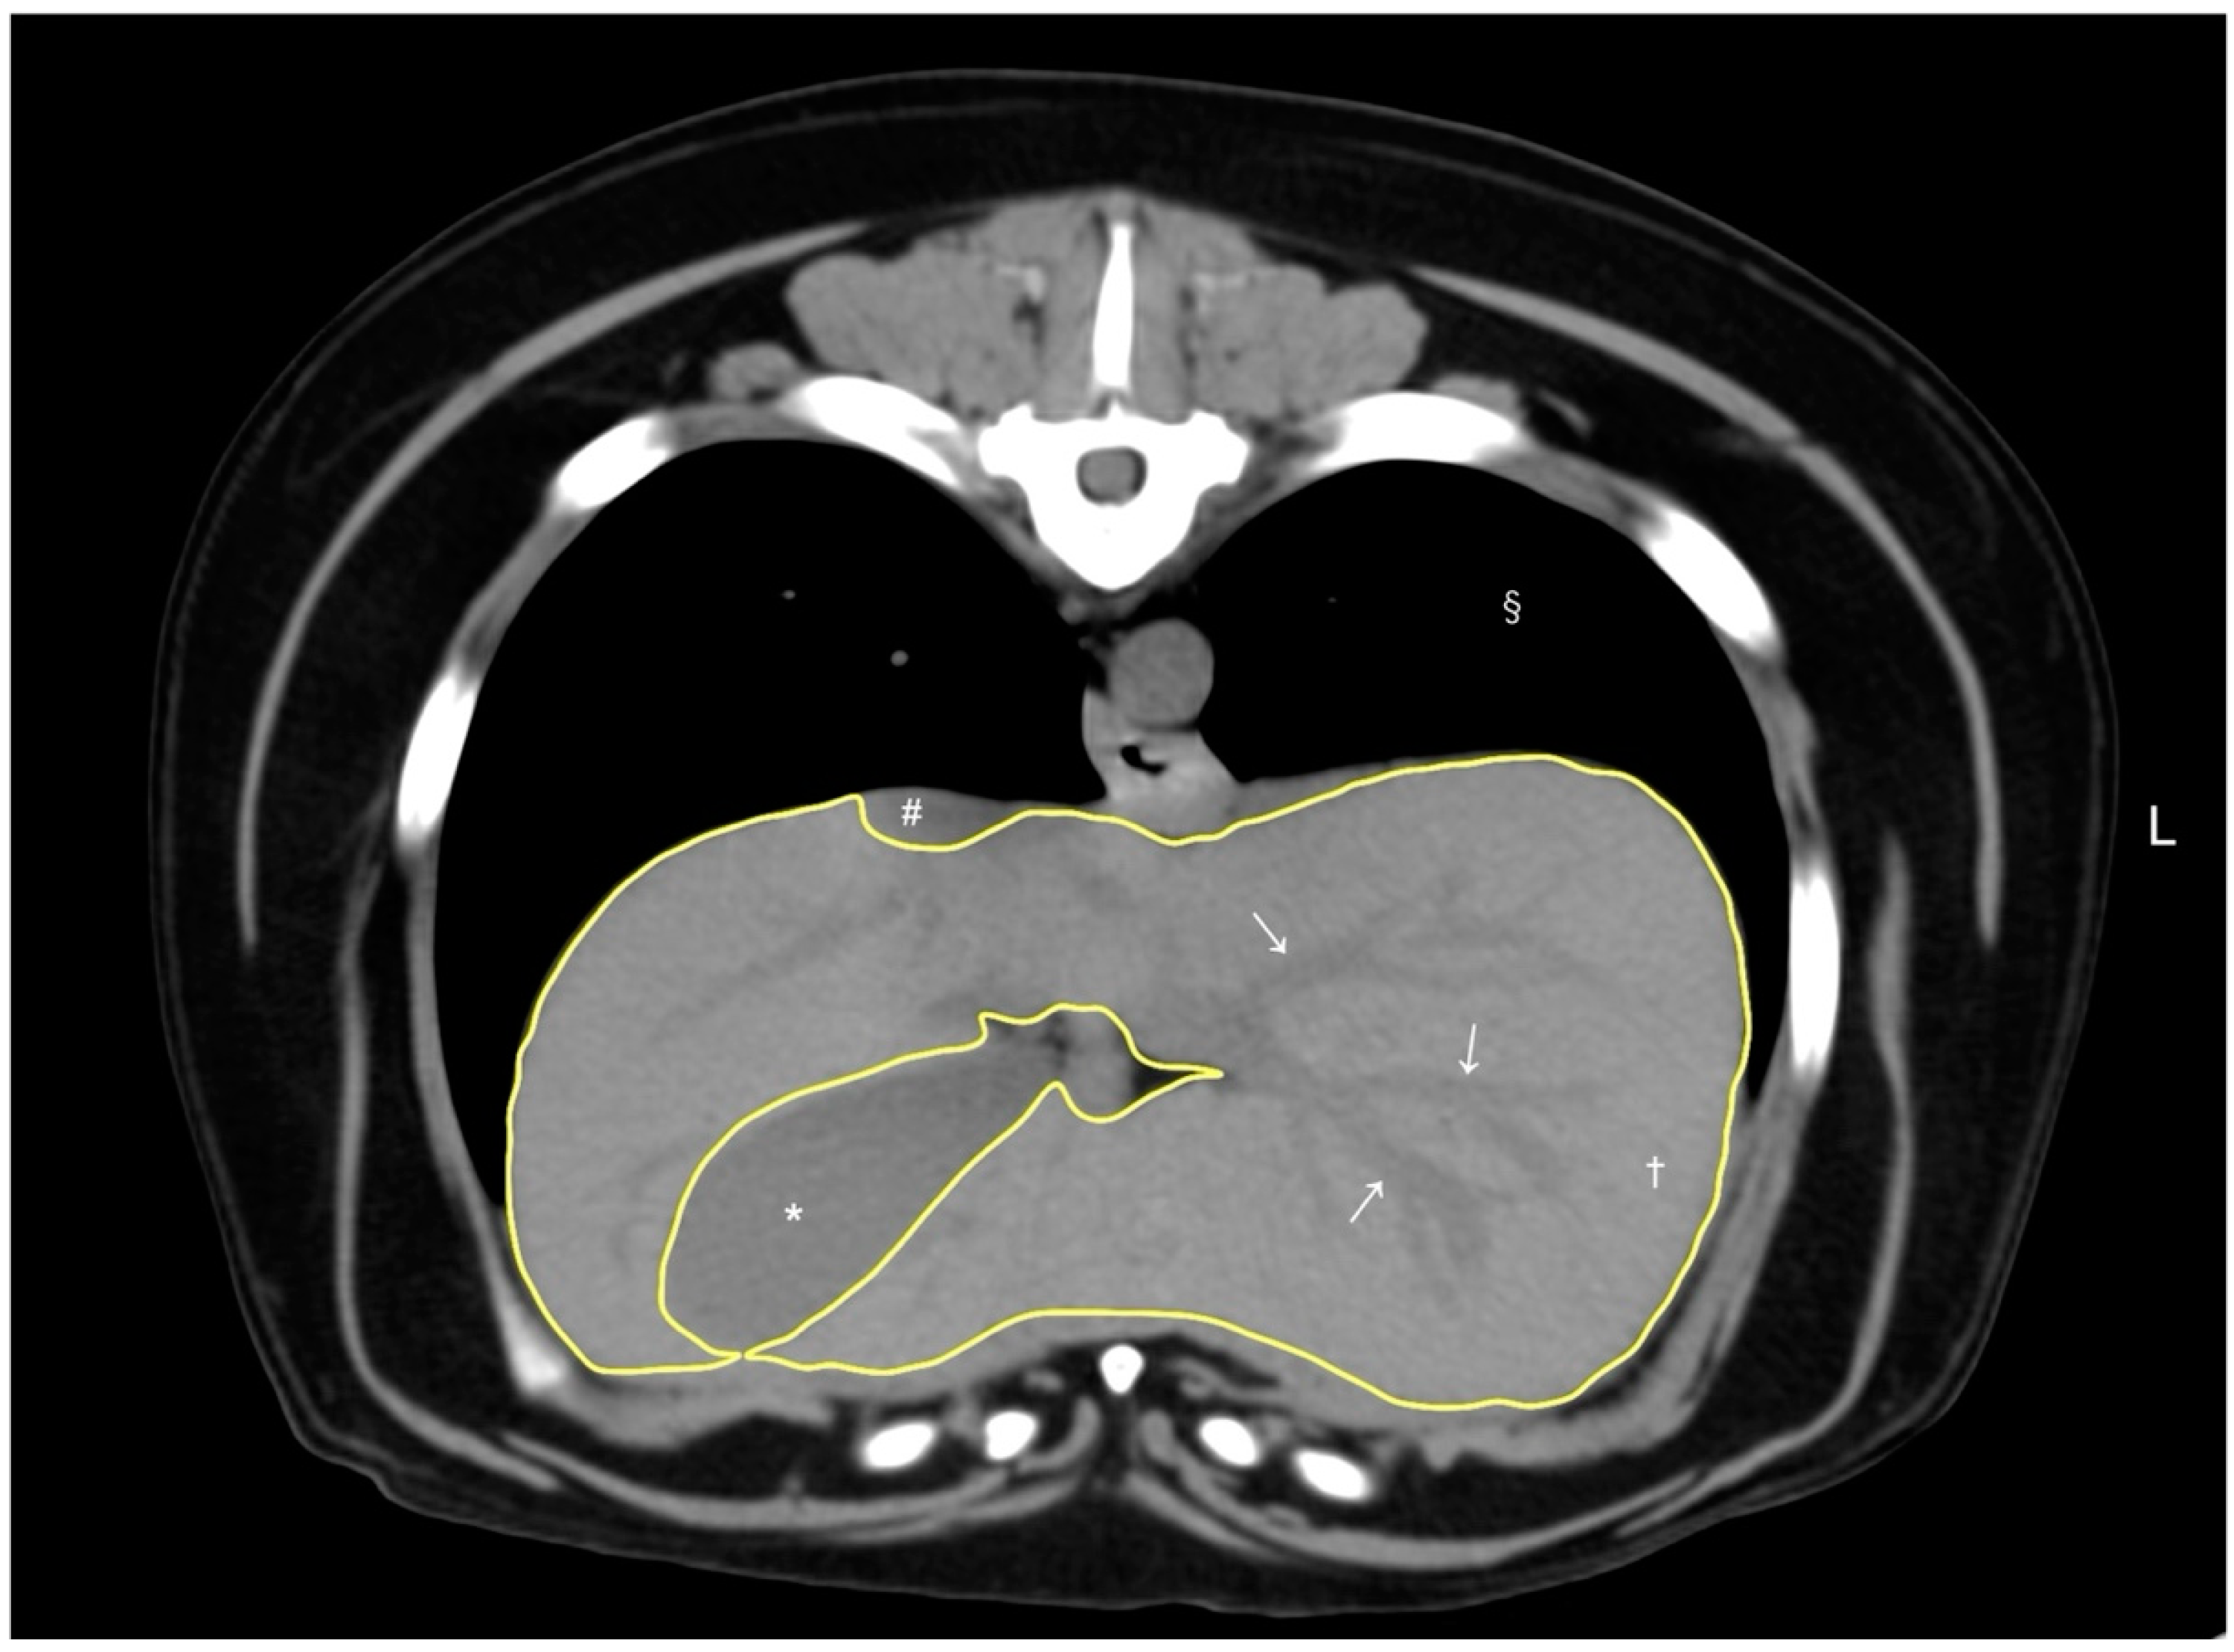

A volumetry of the livers was conducted using CT by a veterinarian (RN) trained under the supervision of the radiologist (MM), using a DICOM viewer (Horos, version 4.0.0., https://horosproject.org [accessed on 12 January 2020]) in accordance with methodologies established in previous studies [8,9]. For all dogs, the window width and window level were adjusted to 350–400 HU and 40 HU, respectively. For liver segmentation, the entire liver was manually delineated into an operator-defined region of interest (ROI) in the transverse plane of the pre-contrast image, extending from the cranial border at the diaphragm to the caudal borders adjacent to the right kidney and spleen. Hepatic vessels within the hepatic parenchyma were included in the ROIs, while visible hepatic lobe fissures, the gallbladder, and hepatic vessels outside the hepatic parenchymal boundary were excluded according to previous reports [8,9]. To enhance efficiency, liver margins were traced instead of filling in the liver parenchyma (Figure 1). After manually outlining the ROIs on more than 20 slices with equal interslice gaps, the liver volume derived by CT was obtained using the following formula: Σ {each slice area (cm2) × slice thickness (cm)} × total number of slices of hepatic parenchyma/number of slices used for calculation, following the protocols from previous reports [8]. Finally, the CT-based liver volume was divided by the dog’s body weight (kg) to determine the normalized CT-based liver volume for each case, as body weight has been reported to be the best normalization factor for liver volumetry [9].

Figure 1. A representative image of abdominal CT transverse pre-contrast images using CT liver volumetry in dogs. The window width and window level were adjusted to 350–400 HU and 40 HU, respectively. The liver segmentation was manually traced as a region of interest (ROI, yellow line). Hepatic vessels (white arrows) within the hepatic parenchyma (†) were included in the ROI, whereas the gallbladder (*), visible liver lobe fissures, and hepatic vessels outside the hepatic parenchymal margin were excluded. The caudal vena cava (#) and pulmonary parenchyma (§) were also noted.